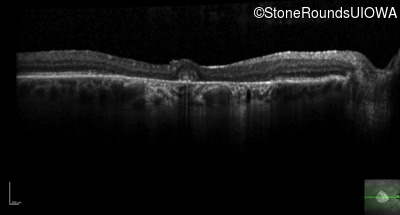

Optical Coherence Tomography - Left - 20/80 +1

Exemplar / OCT Stack

OCT Stack